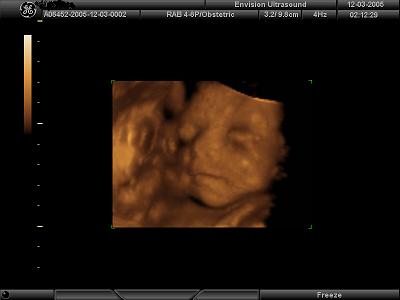

I got great pics at 26 weeks. They say not before 25. Just hit the FAQ section and this website will give you some guidelines..........I attached my 26 week pics so you can get an idea.....

Image Attachment(s):